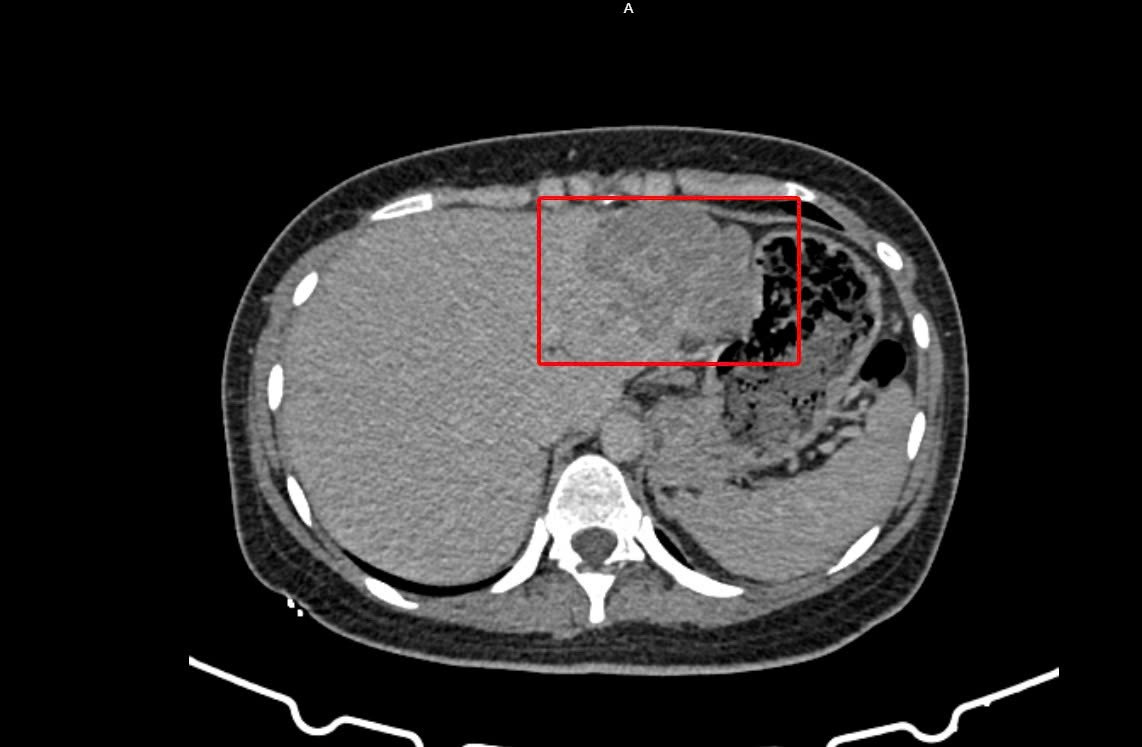

Vùng gan bị tổn thương trên hình ảnh kiểm tra được các bác sĩ ghi nhận

Kết quả cho thấy bệnh nhân bị viêm gan siêu vi B, đồng thời chỉ số AFP (dấu ấn quan trọng trong tầm soát ung thư gan) tăng cao. Hình ảnh CT-Scan bụng có cản quang cũng ghi nhận tổn thương phù hợp với u gan, ung thư biểu mô tế bào gan.